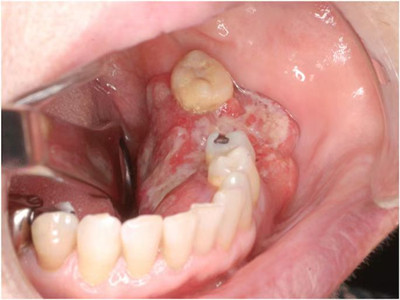

牙龈癌多源于牙间乳头及龈缘区,溃疡呈表浅、淡红,以后可出现增生。由于黏骨膜与牙槽突附着甚紧,较易早期侵犯牙槽突骨膜及骨质,进而出现牙松动,并可发生脱落。X线片可出现恶性肿瘤的破坏特征虫蚀状不规则吸收。

牙龈癌常发生继发感染,肿瘤伴以坏死组织,触之易出血。体积过大时可出现面部肿胀,浸润皮肤。